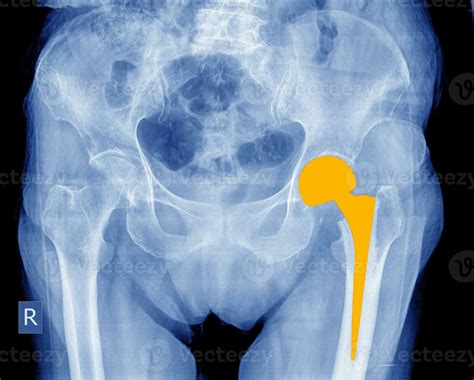

• Total Hip Replacement (THR): This involves replacing both the acetabulum (socket) and the femoral head (ball) with artificial components.

• Hemiarthroplasty: This procedure replaces only the femoral head, leaving the acetabulum intact.

• Revision Hip Replacement: This is performed to replace a previously implanted hip prosthesis that has failed or worn out.

• hip replacement xray normal

• xray of hip replacement

• hip replacement xray female

• total hip replacement on xray

• right hip replacement xray

• total hip vs hemiarthroplasty xray